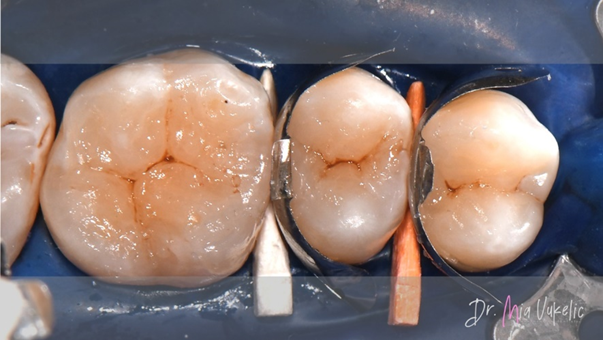

For the restoration of the proximal wall, Ultradent Products’ Halo™ matrices and Ultradent Products’ Halo™ ring were used.

The modified centripetal build-up technique was employed. The initial step involved applying a layer of flowable composite with a thickness of 0.5 mm (Tetric EvoFlow™, Ivoclar*).

The material used for the restoration was Transcend™ composite (Ultradent Products). The proximal wall was created with the EW shade, while the subsequent two horizontal layers were in the A3D shade. Secondary characteristics were achieved using Kolor + Plus™ color modifier - brown (Kerr*).